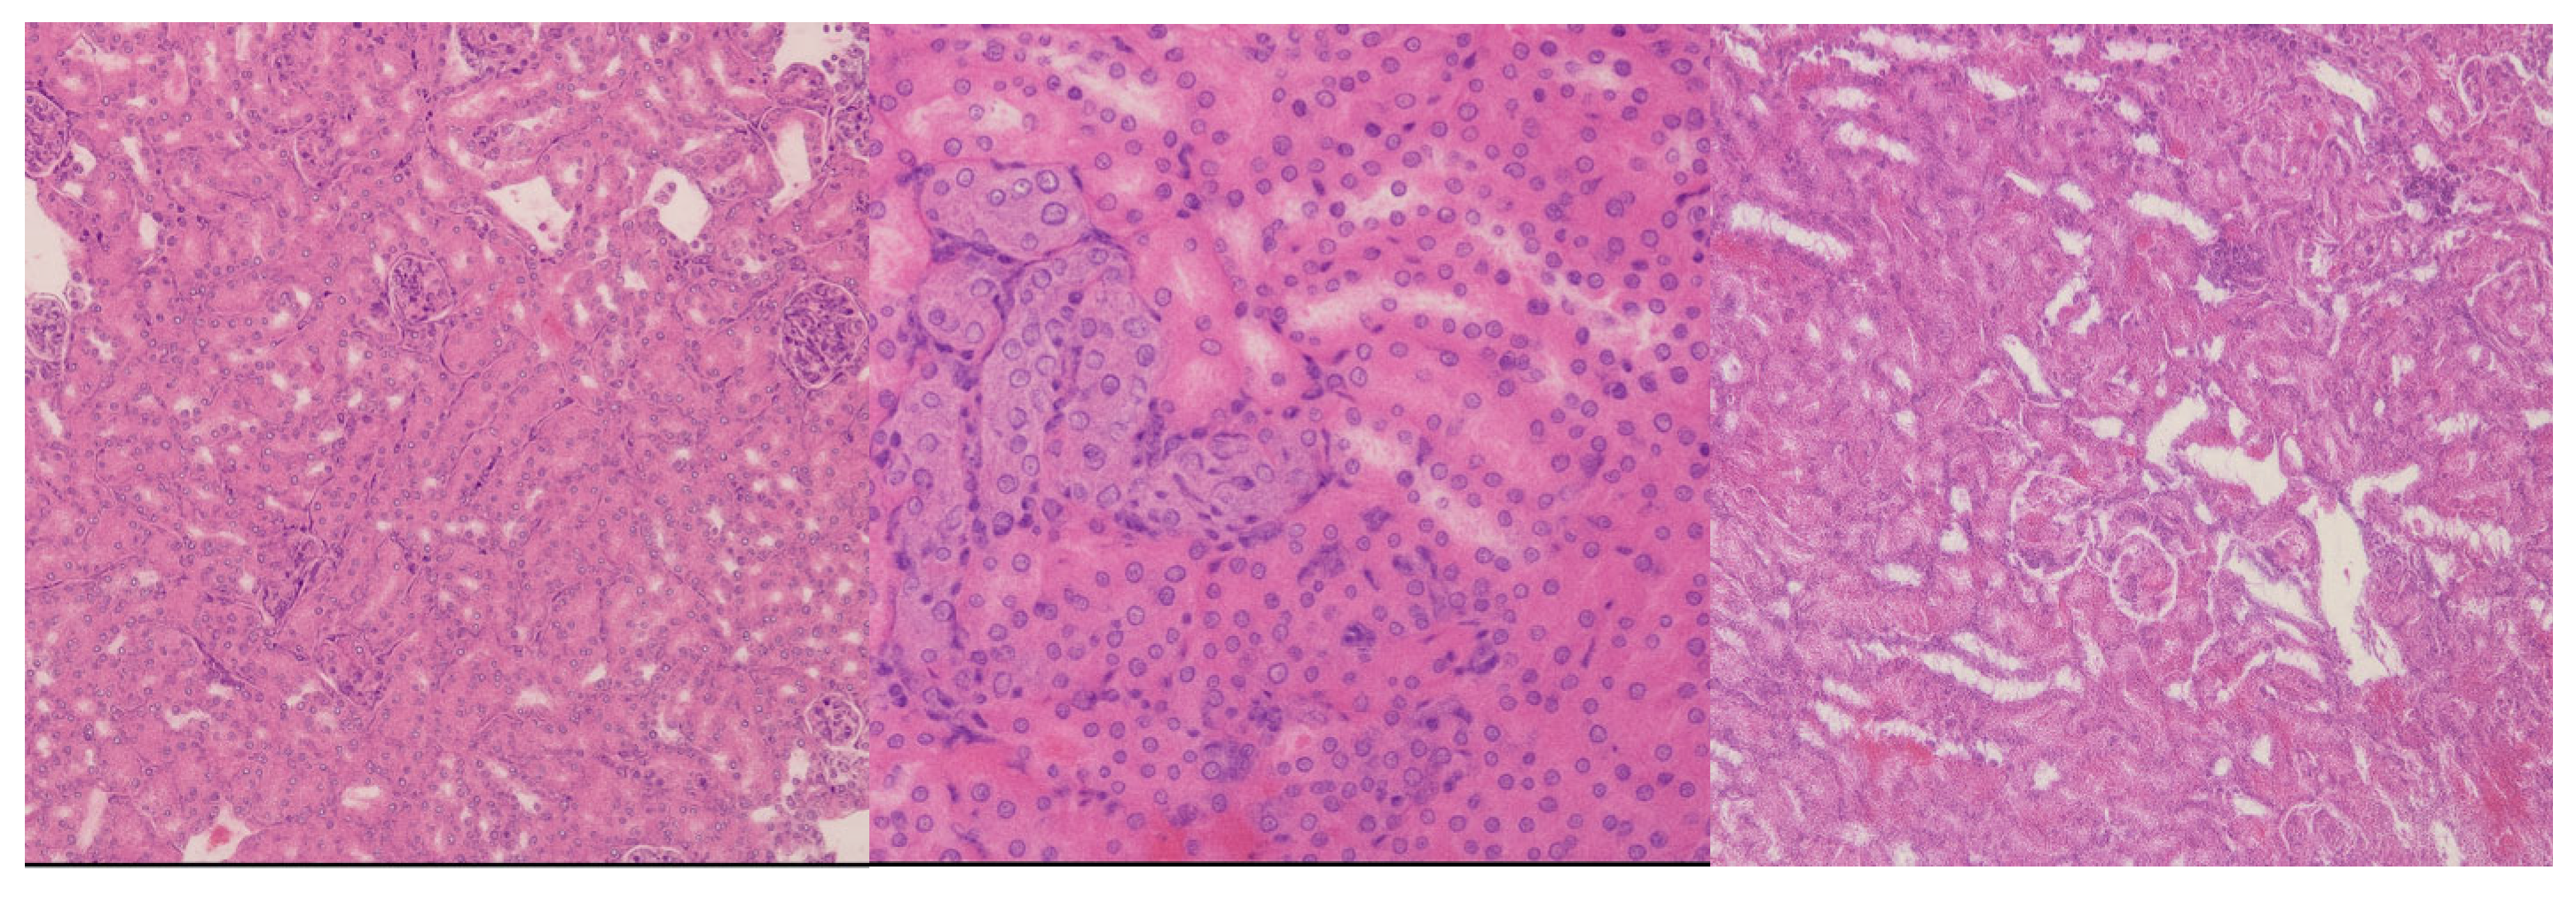

In the liver, the 10 mg/kg and 20 mg/kg groups exhibited preserved hepatic architecture (

Figure 2A). Occasional extramedullary hematopoietic foci were noted, which is a common finding in murine livers. At the highest dose (50 mg/kg), eosinophilic amyloid-like deposits were identified in the space of Disse, accompanied by local hepatocellular atrophy. These findings suggest hepatic stress or altered protein turnover at higher exposure levels. This may be evidence of focal hepatocellular alterations, accompanied by mild periportal inflammatory infiltration, suggestive of early hepatic stress or immune activation.